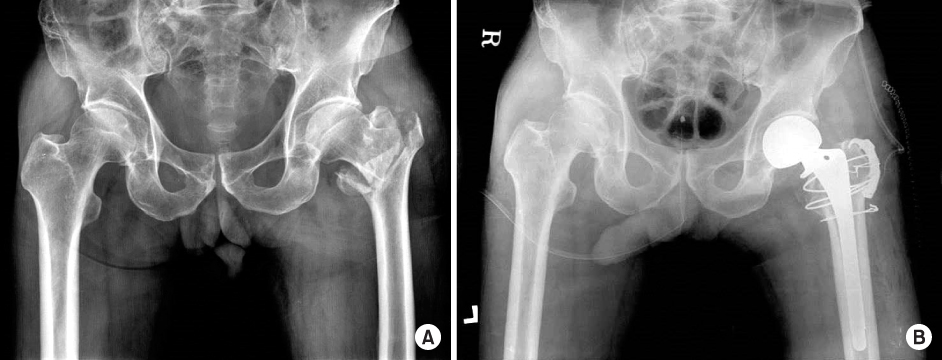

Fig. 2

(A) Preoperative radiograph of type A greater trochater (GT) fracture in a 78-year-old male. (B) Postoperative radiograph of a type A GT fracture fixed with a greater trochanteric reattachment plate.

Fig. 2 (A) Preoperative radiograph of type A greater trochater (GT) fracture in a 78-year-old male. (B) Postoperative radiograph of a type A GT fracture fixed with a greater trochanteric reattachment plate.